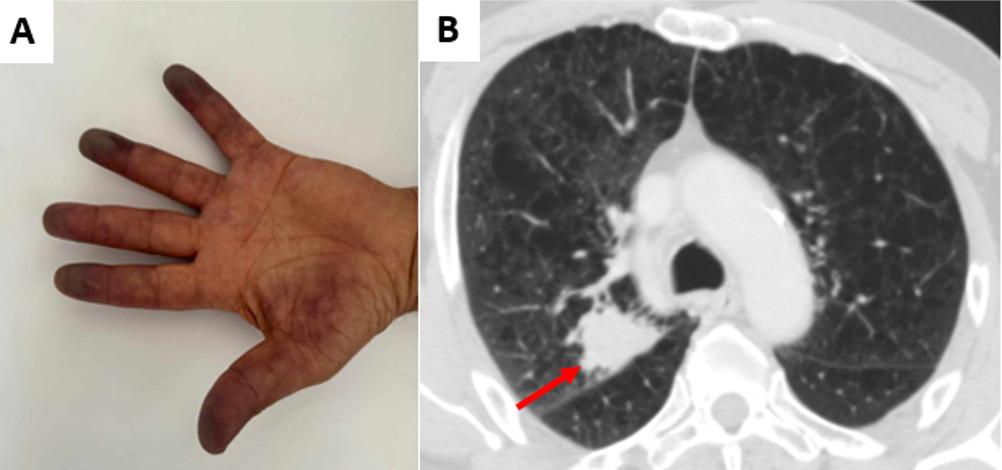

Paraneoplastic Raynaud’s phenomenon revealing lung adenocarcinoma

Soumaya Debiche, Hela Cherif, Tayssir Bachta, Salma Mokaddem, Ferdaous Yangui, Mohamed Ridha Charfi